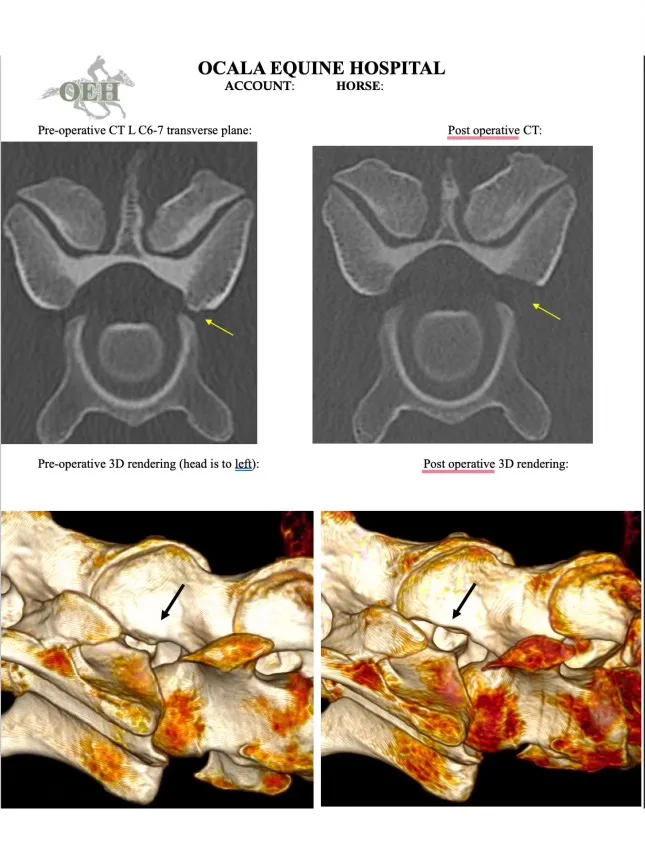

The week after Carolina, Furlong referred Rocky to the team at Ocala Equine Hospital, where Travis Tull, DVM, DACVS, consulted. After Rocky’s CT scan—which gives a comprehensive 3-D view—Tull confirmed Furlong’s initial suspicion. Rocky was indeed experiencing compression in one area where his spinal nerves exit the spinal column, resulting in cervical radiculopathy. In layman’s terms, Rocky had a pinched nerve in his neck that was likely causing pain and interfering with the mobility of his left foreleg.

“The most common cause in horses is an enlarged articular process joint, which are paired joints between the vertebrae on either side of the spinal canal,” Tull explained. “The enlargement can cause a narrowing of the opening where the cervical spinal nerve travels to relay information to and from the spinal cord.”

During Rocky’s assessment at Ocala Equine, an additional treatment option had been presented—a newer procedure called a percutaneous single portal endoscopic foraminotomy. Pioneered by German veterinarian Dr. Jan-Hein Swagemakers in 2020, in a foraminotomy, surgeons insert a specialized endoscope alongside the affected articular process joint through a small incision in the skin, then use various tools to remove the excess bone, create more space and reduce pinching of the nerve. Horses tend to do well following the procedure; rehabilitation begins just three days later, and most are back in ridden work after six weeks.

Rocky’s connections knew the gelding would be in capable hands with Tull. In August 2023, Tull had performed the first foraminotomy in the United States; since then, he has taught 18 other veterinarians how to do the procedure. Ocala Equine is one of just eight hospitals nationwide currently offering foraminotomy, but Tull said its availability has improved the possible outcomes for horses experiencing cervical radiculopathy.

“Before the advent of foraminotomy, the only options were medical treatment or cervical spinal fusion,” he said. “After foraminotomy surgery, horses are rehabilitated to improve their mobility, proprioception and core muscular strength.”